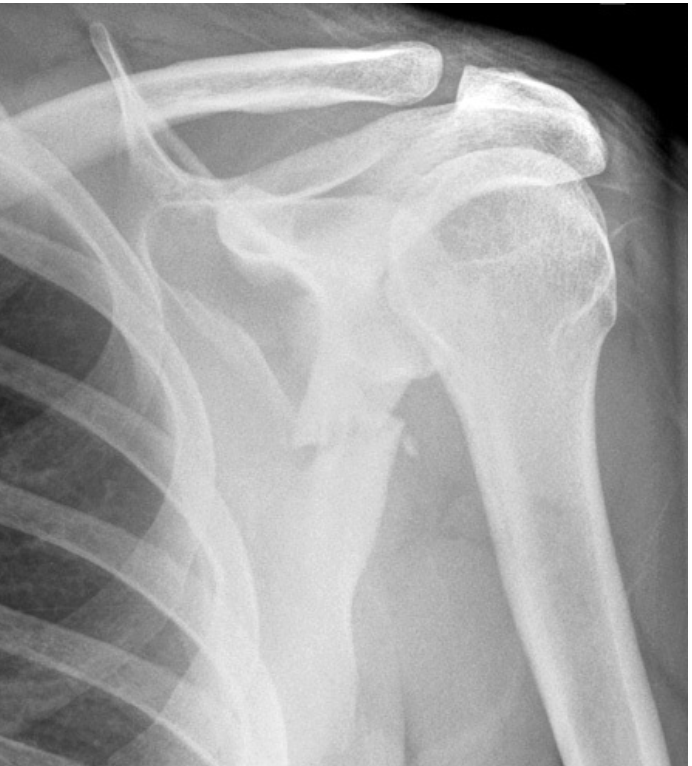

Label the following diagram

1. Spine of scapula

2. Clavicle

3. Acromioin

4. Humerus head

5. GH joint

6. Shaft of humerus

7. Medial boarder of scapula

8. Humeral head (greater tuberosity)

9. acromion

10. GH joint

11. Lateral boarder of scapula

12. clavicle

13. coracoid process